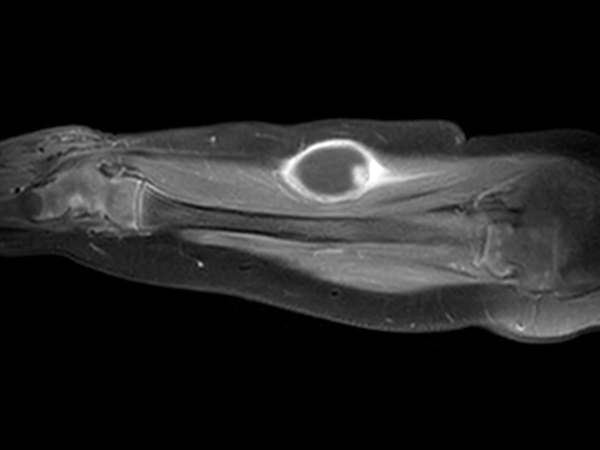

Pediatric forearm with lesion

Pediatric patient with a lesion in the forearm. mDIXON XD provides uniform fat-free imaging and allows for multiple image types in one single scan. Integration of Compressed SENSE acceleration technique enables speeding up of the entire exam.

Axial T1w TSECompressed SENSE